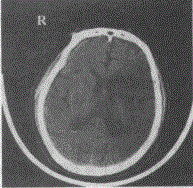

问题 某高血压患者出现偏瘫,CT如图,该患者可能出现下列哪种表现

选项 A.左侧肢体无力 B.右侧肢体无力 C.左侧肢体感觉减退 D.胸4以下感觉减退 E.双侧下肢振动觉消失

答案 B